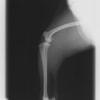

術前側面像

術後側面像

術前に25°であったTPAは、TPLO実施により7°に矯正されました。症例の歩行状態は良好です。